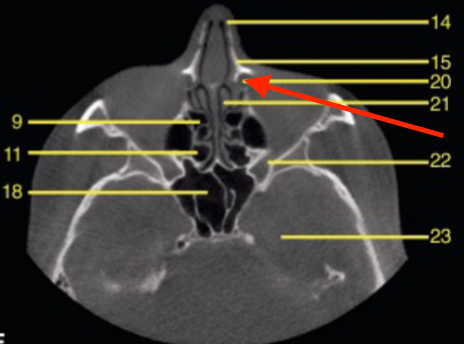

identify the structure

zygomatic arch

what is indicated by the YELLOW

middle turbinates/concha

nasolacrimal duct

maxillary sinus

what is indicated by the GREEN dot

axial

what plane is this

level of maxilla (above maxillary teeth)

at what level is this